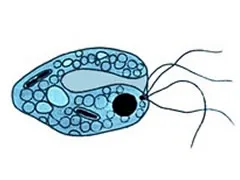

Lamblioza (Giardia lamblia)

Lamblioza to choroba pasożytnicza, która wywoływana jest pierwotniakiem Giardia lamblia. jest chorobą przenoszoną drogą pokarmową. Do zarażenia dochodzi poprzez niezachowanie odpowiedniej higieny, picie skażonej wody oraz zjedzenie pokarmów, np. jarzyn i owoców, na których znajdują się cysty pierwotniaka Giardia lamblia. Możliwe jest także przeniesienie choroby z osoby na osobę. Gdy już dojdzie do zarażenia, pierwotniak ten umieszcza się

w przewodzie pokarmowym oraz w przewodach trzustkowych i drogach żółciowych, gdzie zaczyna się rozmnażać.

Lamblia składa się z 4 wici, dzięki którym może się poruszać, a w części brzusznej bieguna przedniego posiada przyssawkę, która umożliwia przyczepienie się do błony śluzowej przewodu pokarmowego żywiciela. Rozmnażanie się poprzez podział podłużny, dzięki któremu możliwe jest szybkie zwiększenie ich liczby w jelicie. W przypadku niesprzyjających warunków, pewna liczba pasożytów otacza się grubą otoczką i tworzy owalne cysty. Człowiek bardzo często zaraża się tymi pasożytami przez spożycie jarzyn i owoców lub picie zanieczyszczonej wody. Cysty mogą znajdować się wewnątrz oraz na powierzchni produktów spożywczych przechowywanych w złych warunkach sanitarnych. Transmisja z człowieka na człowieka jest możliwa w czasie kontaktów seksualnych. Do zakażenia może dochodzić również na basenach i w czasie kąpieli w zanieczyszczonych ludzkimi odchodami zbiornikach wodnych.